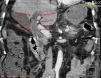

La importancia clínica de los cálculos en las vías biliares radica en su asociación con colangitis y pancreatitis aguda. La colangiografía pancreática retrógrada endoscópica (CPRE) es considerada el método terapéutico más seguro y exitoso para extraer cálculos en el conducto biliar común. No obstante, los cálculos grandes o impactados que ocupan la totalidad del conducto biliar son un reto terapéutico. Se define como cálculo biliar grande aquellos mayores de 10-15mm de tamaño. Existen muy pocos reportes que describan un cálculo único gigante (> 5cm) en el conducto biliar común. Presentamos a una paciente de 58 años que cursó con pancreatitis aguda severa y con hallazgos tomográficos de cálculo biliar impactado, dilatación de las vías biliares y colelitiasis (fig. 1). Se le realizó CPRE, encontrando un lito gigante en el conducto biliar común, ocupando hasta la confluencia de los conductos hepáticos (fig. 2). La paciente fue sometida a una colecistectomía convencional con exploración de vías biliares y hepático-yeyuno anastomosis en Y de Roux, extrayendo un cálculo coraliforme de 7×2cm (figs. 3 y 4). La paciente fue egresada sin complicaciones y se encuentra asintomática 6 meses después de la cirugía, con pruebas de funcionamiento hepático normales.